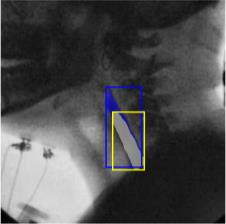

The videofluoroscopic swallowing study (VFSS) is a gold-standard imaging technique for assessing swallowing, but analysis and rating of VFSS recordings is time consuming and requires specialized training and expertise. Researchers have recently demonstrated that it is possible to automatically detect the pharyngeal phase of swallowing and to localize the bolus in VFSS recordings via computer vision, fostering the development of novel techniques for automatic VFSS analysis. However, training of algorithms to perform these tasks requires large amounts of annotated data that are seldom available. We demonstrate that the challenges of pharyngeal phase detection and bolus localization can be solved together using a single approach. We propose a deep-learning framework that jointly tackles pharyngeal phase detection and bolus localization in a weakly-supervised manner, requiring only the initial and final frames of the pharyngeal phase as ground truth annotations for the training. Our approach stems from the observation that bolus presence in the pharynx is the most prominent visual feature upon which to infer whether individual VFSS frames belong to the pharyngeal phase. We conducted extensive experiments with multiple convolutional neural networks (CNNs) on a dataset of 1245 bolus-level clips from 59 healthy subjects. We demonstrated that the pharyngeal phase can be detected with an F1-score higher than 0.9. Moreover, by processing the class activation maps of the CNNs, we were able to localize the bolus with promising results, obtaining correlations with ground truth trajectories higher than 0.9, without any manual annotations of bolus location used for training purposes. Once validated on a larger sample of participants with swallowing disorders, our framework will pave the way for the development of intelligent tools for VFSS analysis to support clinicians in swallowing assessment.